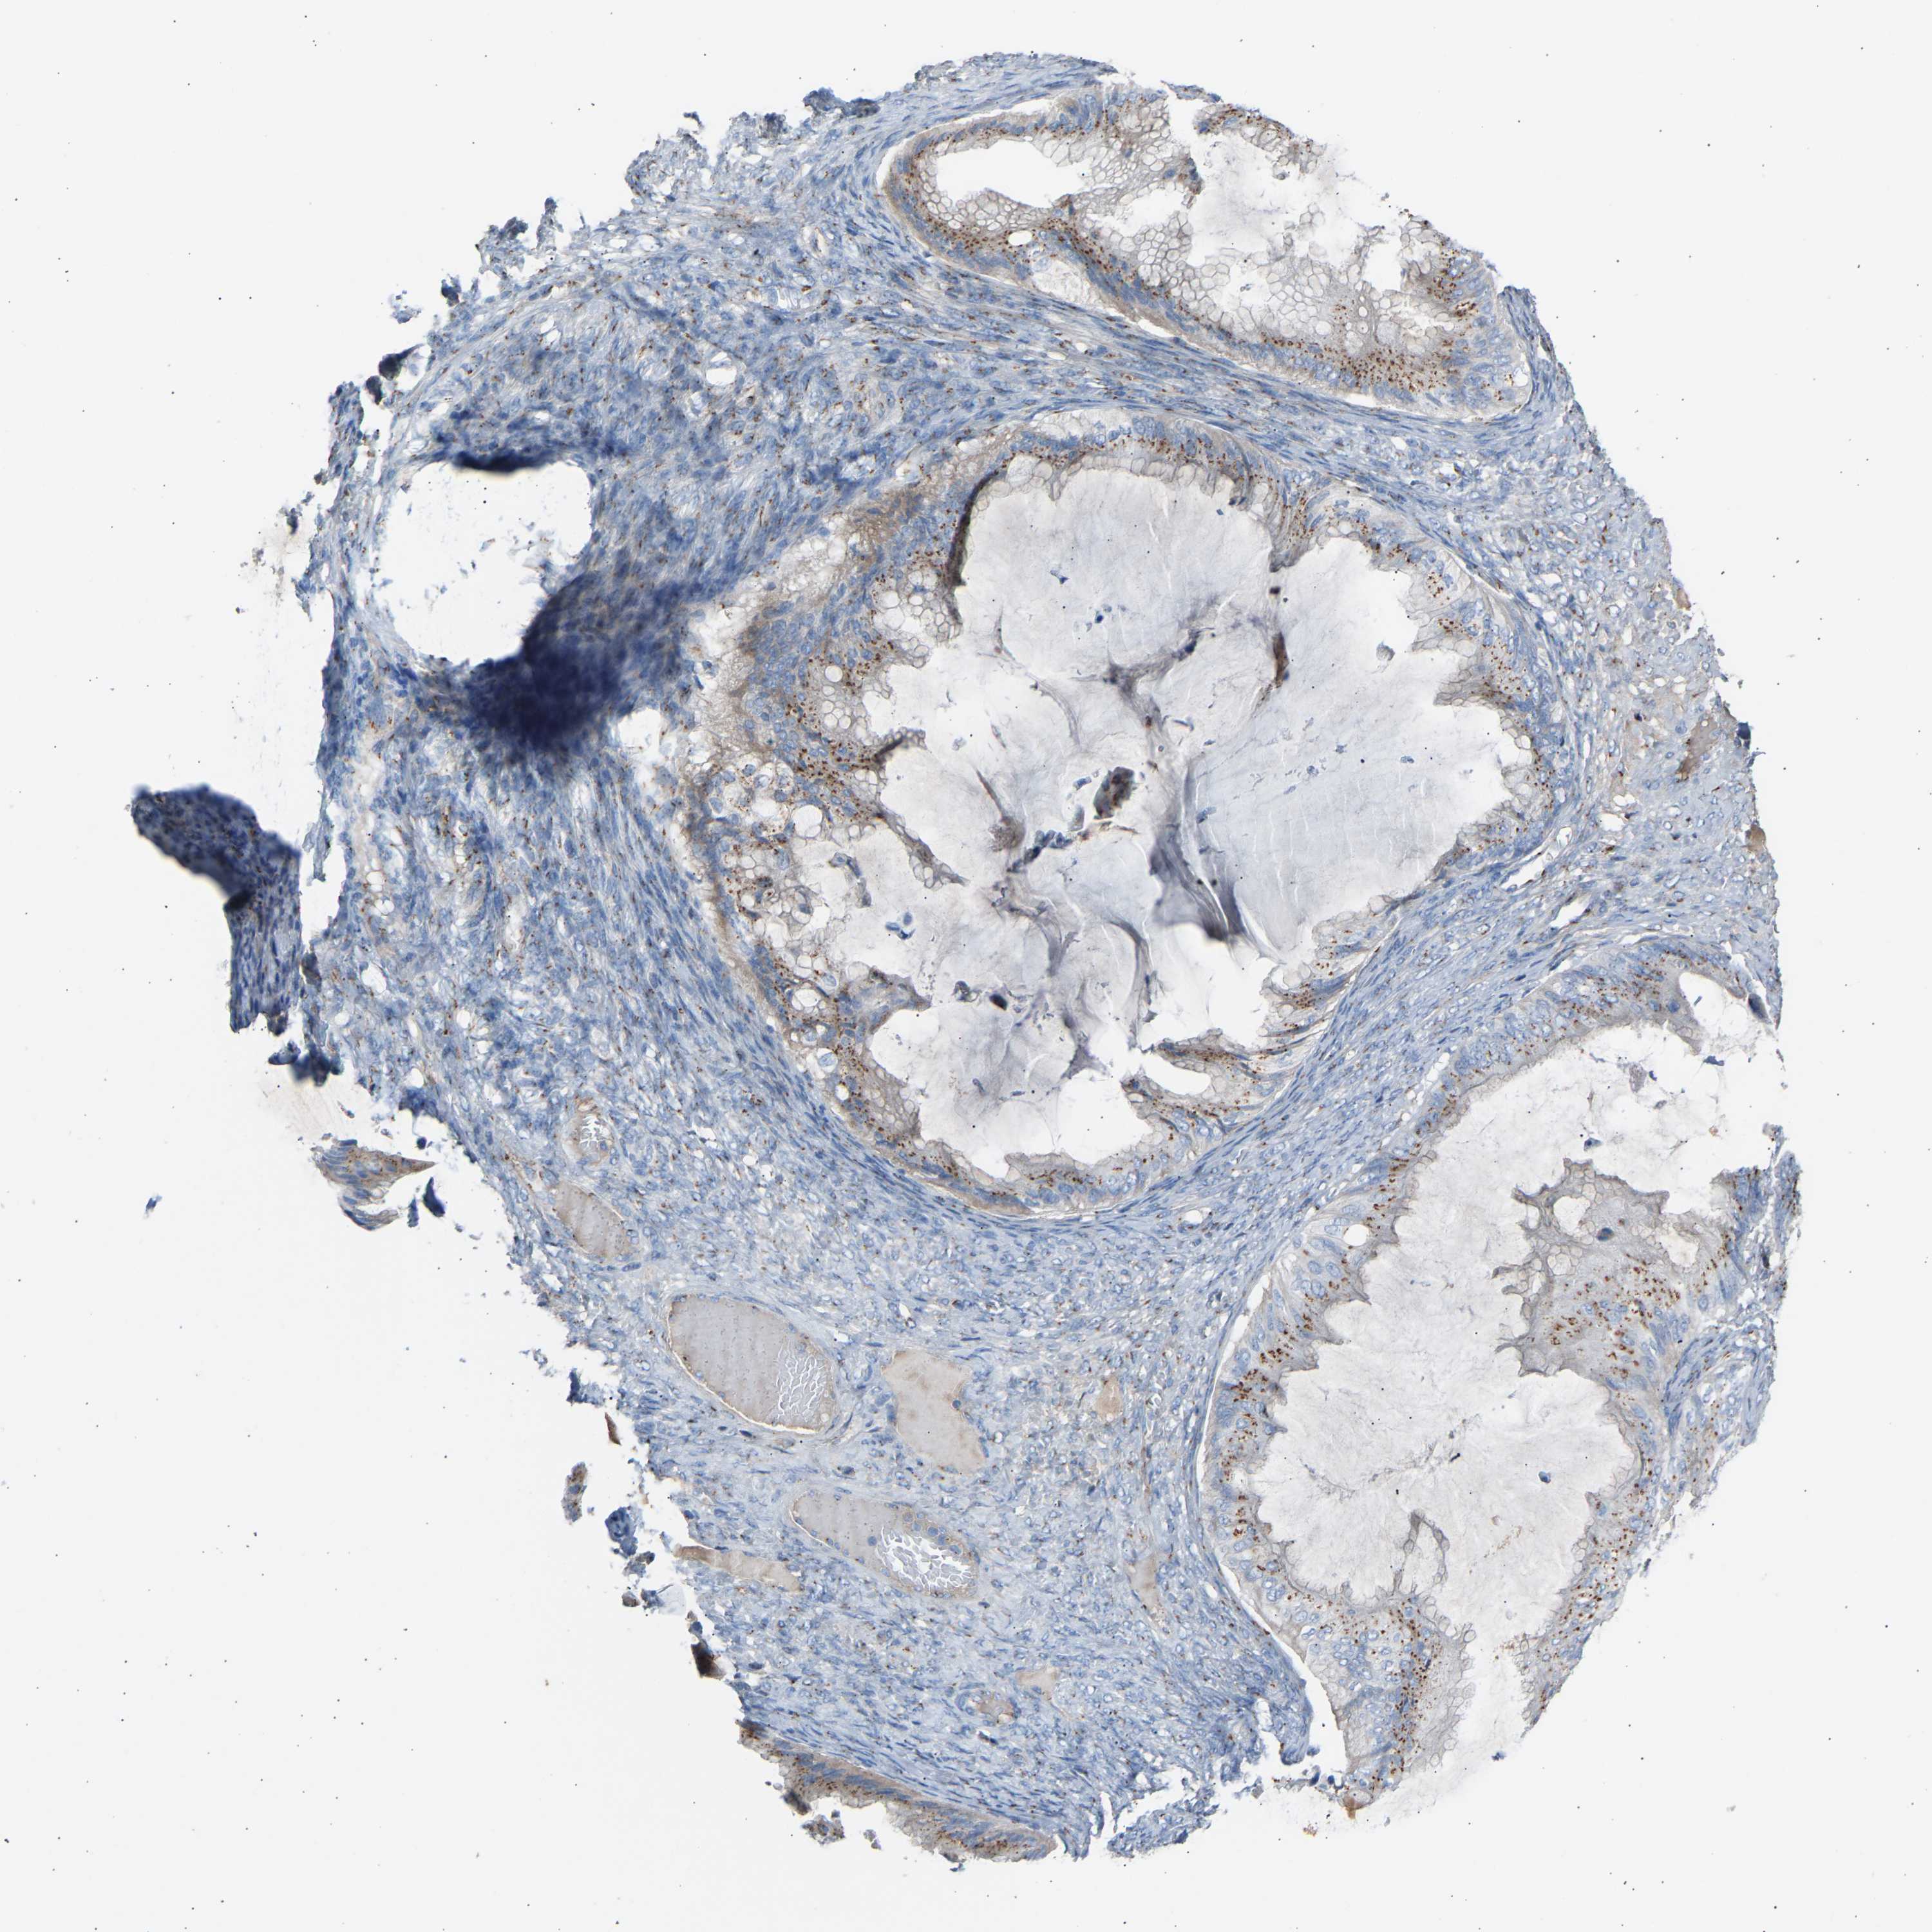

OVARIAN CANCER - Protein expressioni

A mouse-over function shows sample information and annotation data. Click on an image to view it in a full screen mode. Samples can be filtered based on level of antibody staining by selecting one or several of the following categories: high, medium, low and not detected. The assay and annotation is described here.

Note that samples used for immunohistochemistry by the Human Protein Atlas do not correspond to samples in the TCGA dataset.

Antibody stainingi

Antibody staining in the annotated cell types in the current human tissue is reported as not detected, low, medium, or high, based on conventional immunohistochemistry profiling in selected tissues. This score is based on the combination of the staining intensity and fraction of stained cells.

Each image is clickable and will lead to virtual microscopy that enables deeper exploration of all samples and also displays staining intensity scores, fraction scores and subcellular localization as well as patient and tissue information for each sample.

Antibody HPA020060

Cystadenocarcinoma, serous, NOS

Carcinoma, endometroid

Cystadenocarcinoma, mucinous, NOS

Carcinoma, NOS